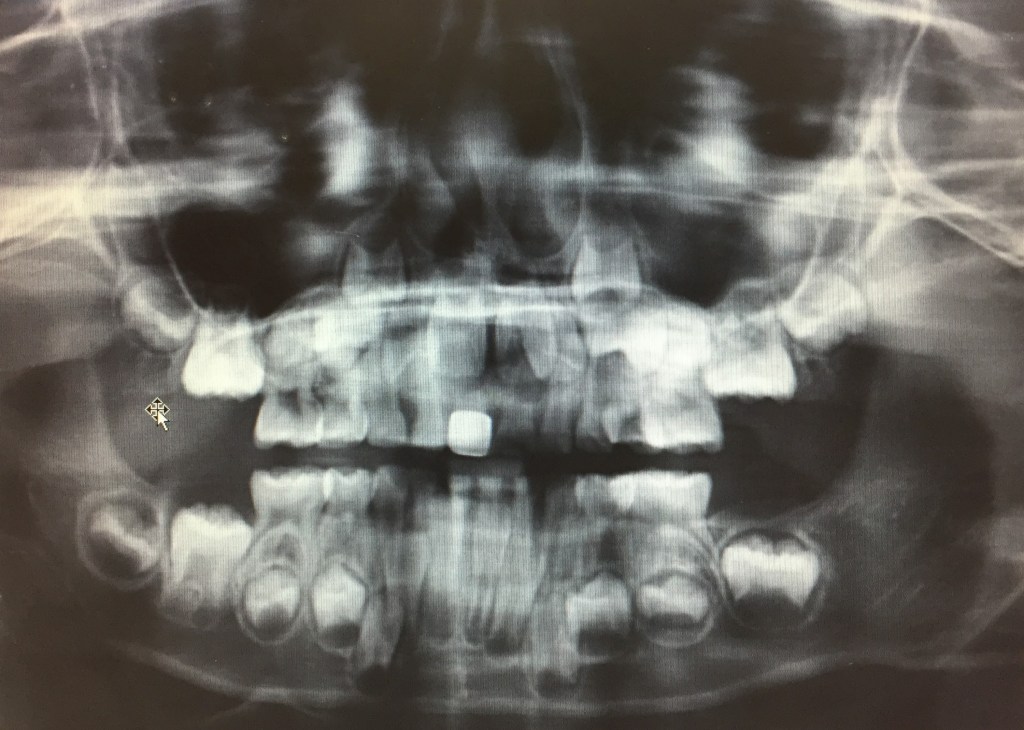

엑스레이에는 잇몸 속에 숨어 있던 영구치들이 모두 보였고, 각 영구치의 상태는 의사의 예상대로였다. 나는 사진이 너무 재밌어서 사진을 가져갈 수는 없냐고 물어봤다. 간호사는 핸드폰으로 찍어 가라고 했다.

사진을 잘 보면 아래쪽 앞니의 영구치가 거의 다 올라온 것을 확인할 수 있는 반면, 위쪽 앞니의 영구치는 아직도 한참 더 올라와야 했다. 숨어 있는 어금니들도 다 보이는데, 제일 재밌는 건 송곳니이다. 위아래의 송곳니들은 아직도 출발선에서 기다리고 있는 듯한 모습.